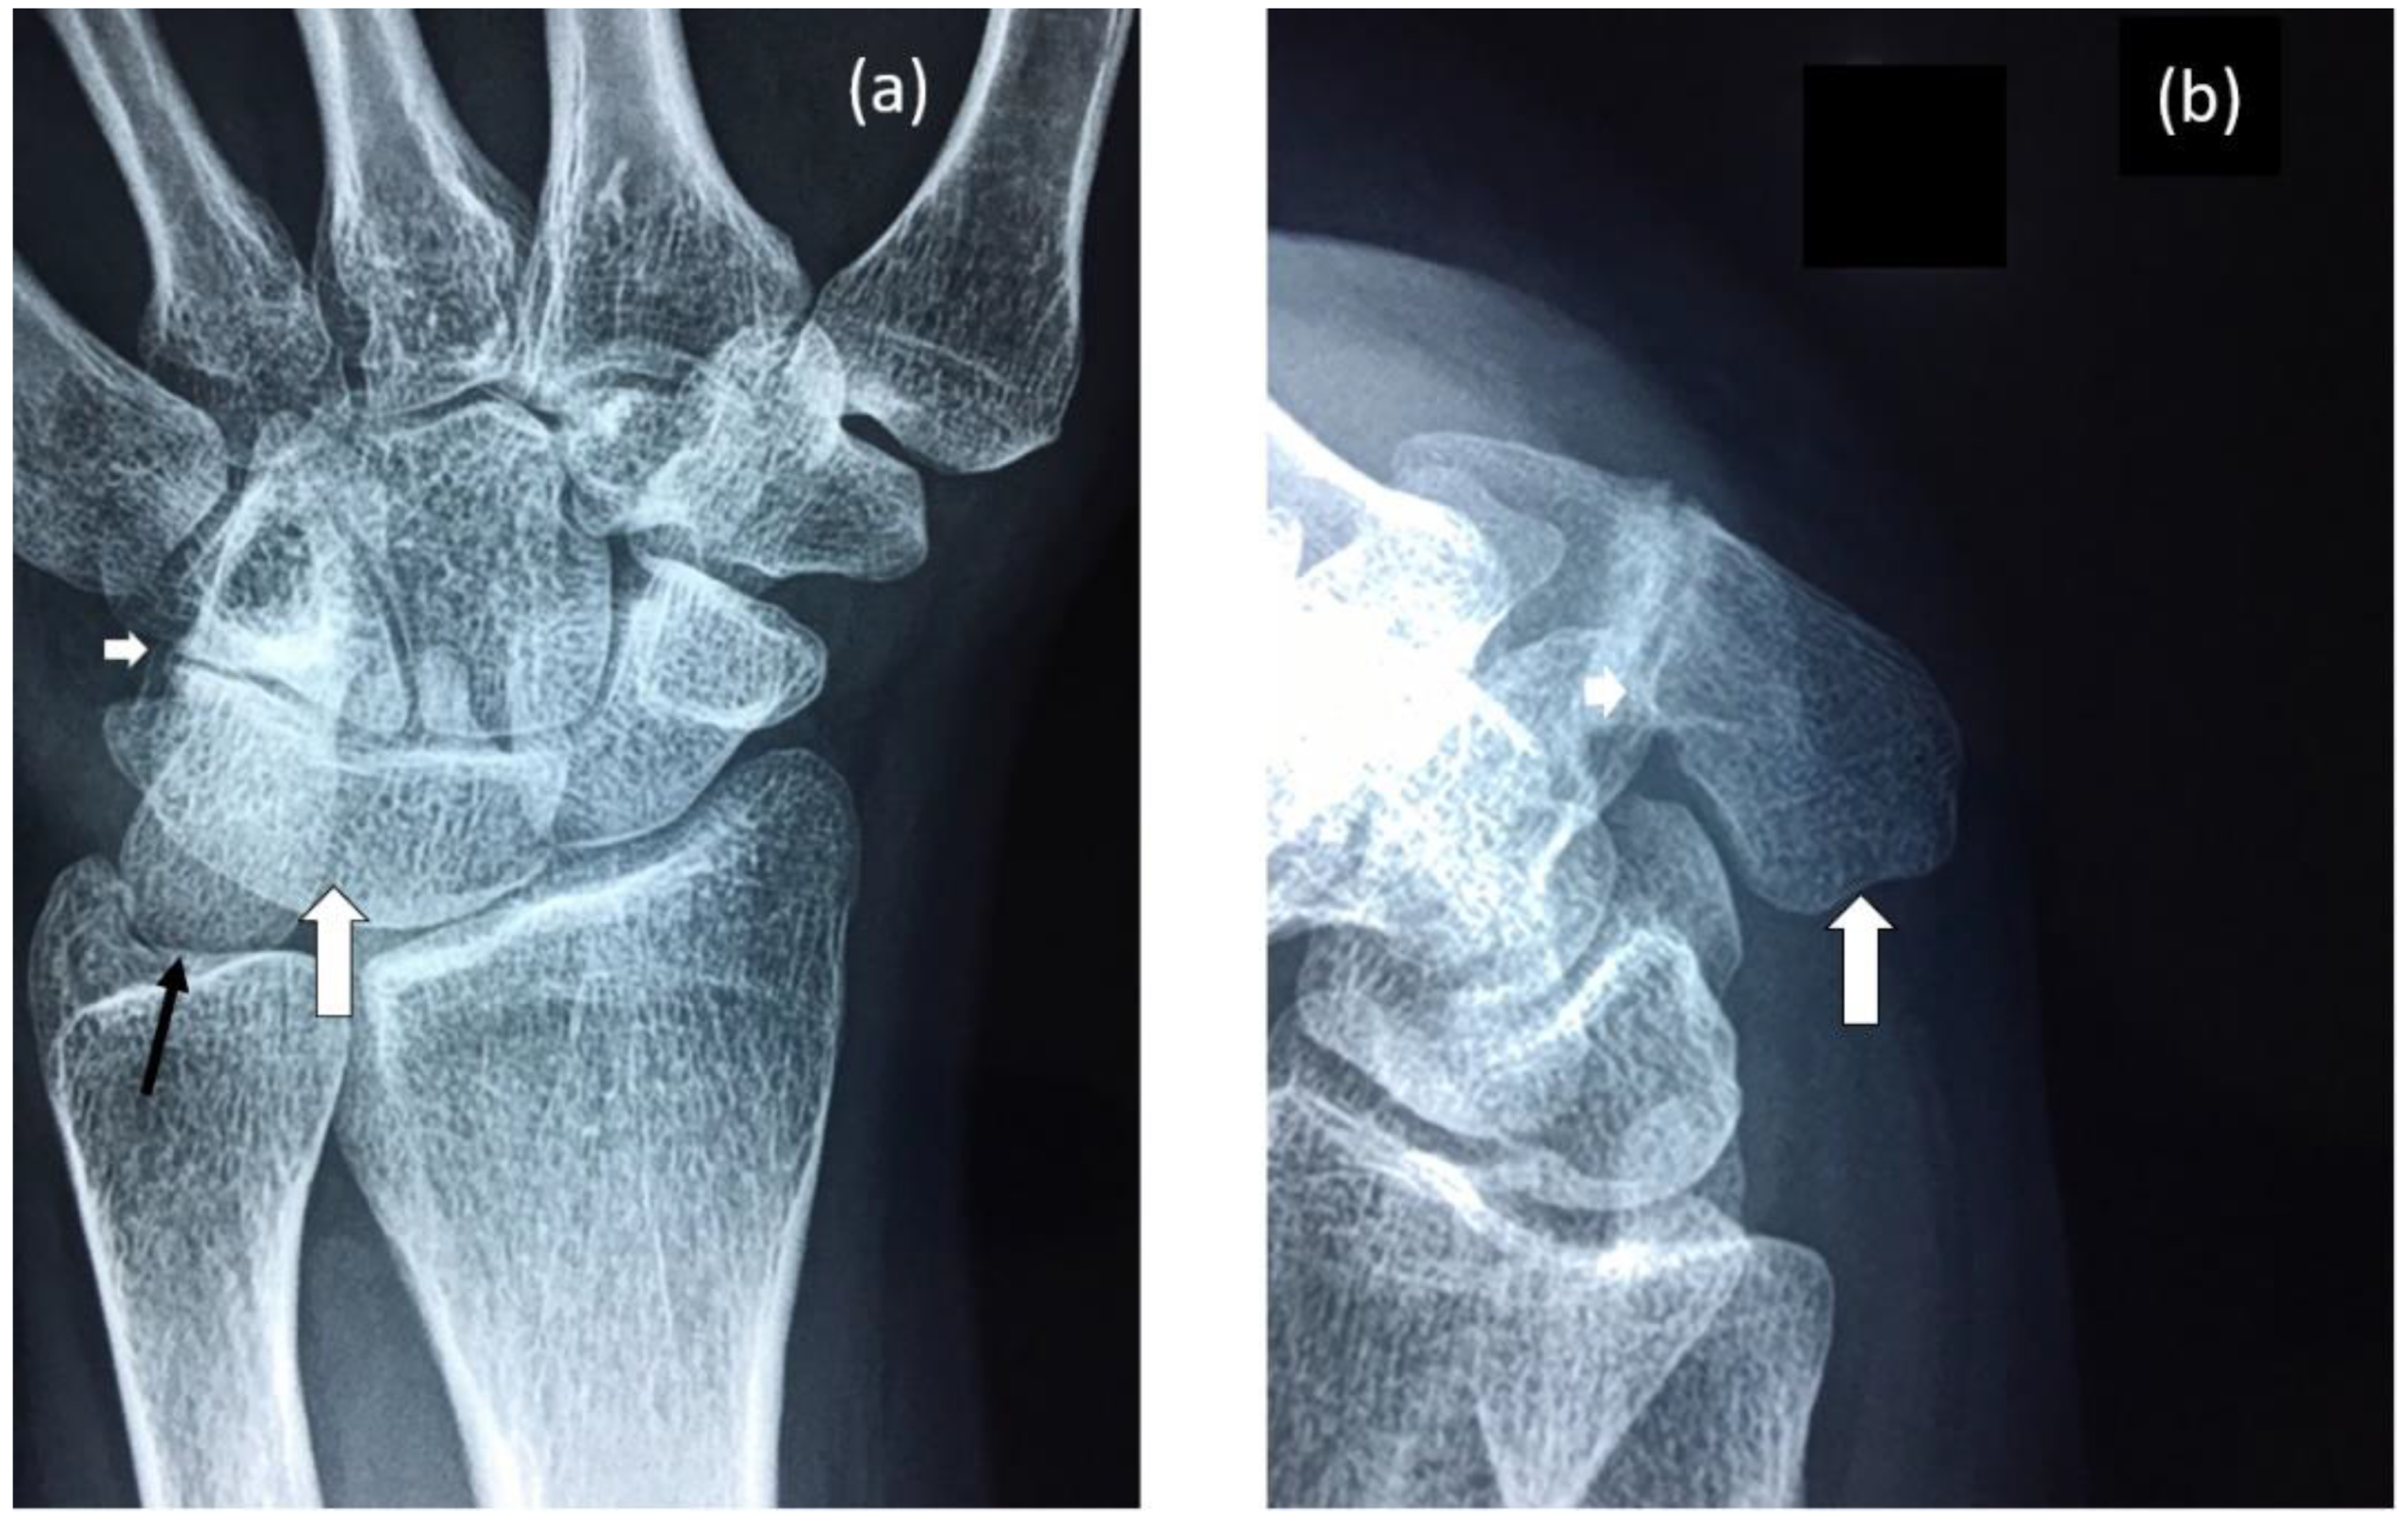

Figure 2.

Radiographs of proband’s wrist highlighting: (a) Fusion of lunate and triquetrum (large white arrow), nearly complete fusion of hamate and pisiform (small white arrow) and elongation of the pisiform (black arrow). (b) Elongated pisiform (large white arrow) and fusion of hamate and pisiform (small white arrow).